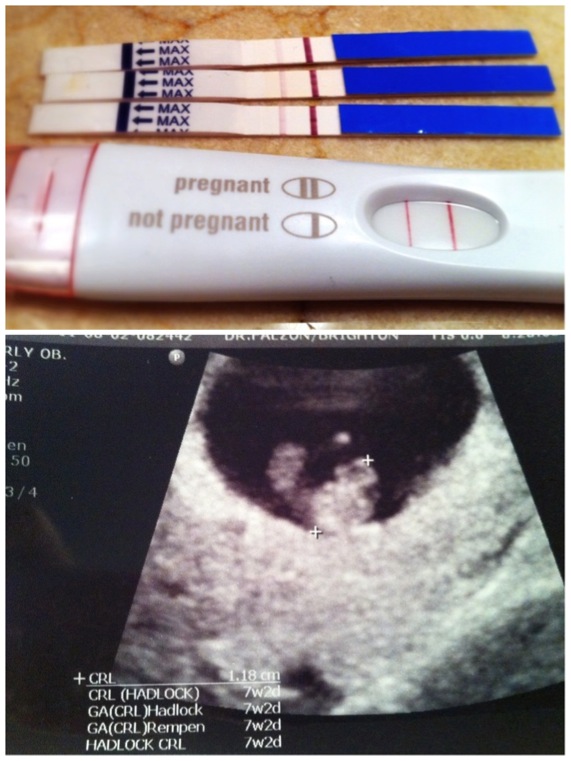

A little bit pregnant. July 2011.

It was a year ago today that we found out I was pregnant with you.  Excitement and elation don't even begin to describe how I felt when I realized you were growing in my belly.  I remember feeling anxious on the Friday night that I decided to take a pregnancy test.  It was still a day or two before my period but I was feeling unusually optimistic that month.  Something just felt different.  I didn't tell your Dad I was going to take one but after dinner I went into the bathroom and took a pregnancy test.  As I was washing my hands, I glanced over at the test strip and saw a faint little second line appearing.  Doing a double take I quickly grabbed the test and ran out to your Dad and asked him...

In all the previous months of taking those tests, I had never seen two lines before.  But I had wanted to so badly.  And now there they were.  Two beautiful little lines full of hope.  Full of promise.  Full of dreams.  I was finally pregnant and I was so excited to meet you.  Your birth day couldn't come quickly enough.  Those nine and a half months were, at times, excruciatingly long but I wouldn't change a thing.